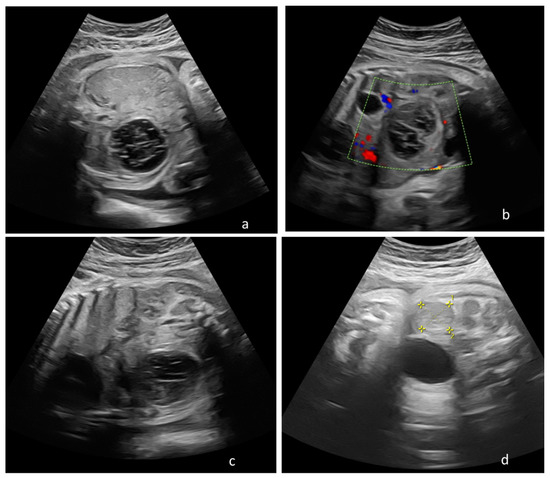

The surgical approach was necessary after complications were suspected following ultrasound or fetal MRI, especially for complex cysts. The main surgical indication was ovarian torsion that was confirmed in eight cases, all with right ovarian cysts. We acknowledge that seven children with confirmed ovarian torsion did not have an acute abdomen at birth (Figure 2). Only one infant presented surgical abdomen four days after birth. In another three children, surgery was performed following the worrying increase in size of the ovarian cyst and intracystic bleeding during the first seven days after birth.

Figure 2. Ovarian torsion. (a) Postnatal abdominal ultrasound with enlarged, inhomogeneous structure without vascular Doppler signal; and (b) a cyst with fluid-fluid level.